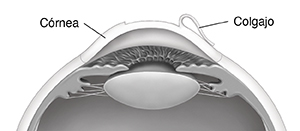

Tal vez sienta presión, pero no dolor, a medida que el cirujano le crea el colgajo en la capa superior de la córnea (el epitelio). El colgajo se voltea hacia atrás, pero queda adherido a la córnea.